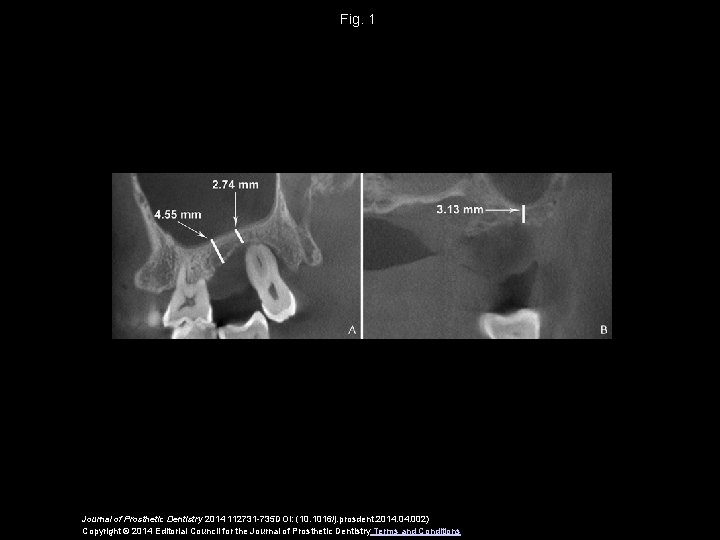

Fig. 1 Journal of Prosthetic Dentistry 2014 112731 -735 DOI: (10. 1016/j. prosdent. 2014. 002) Copyright © 2014 Editorial Council for the Journal of Prosthetic Dentistry Terms and Conditions